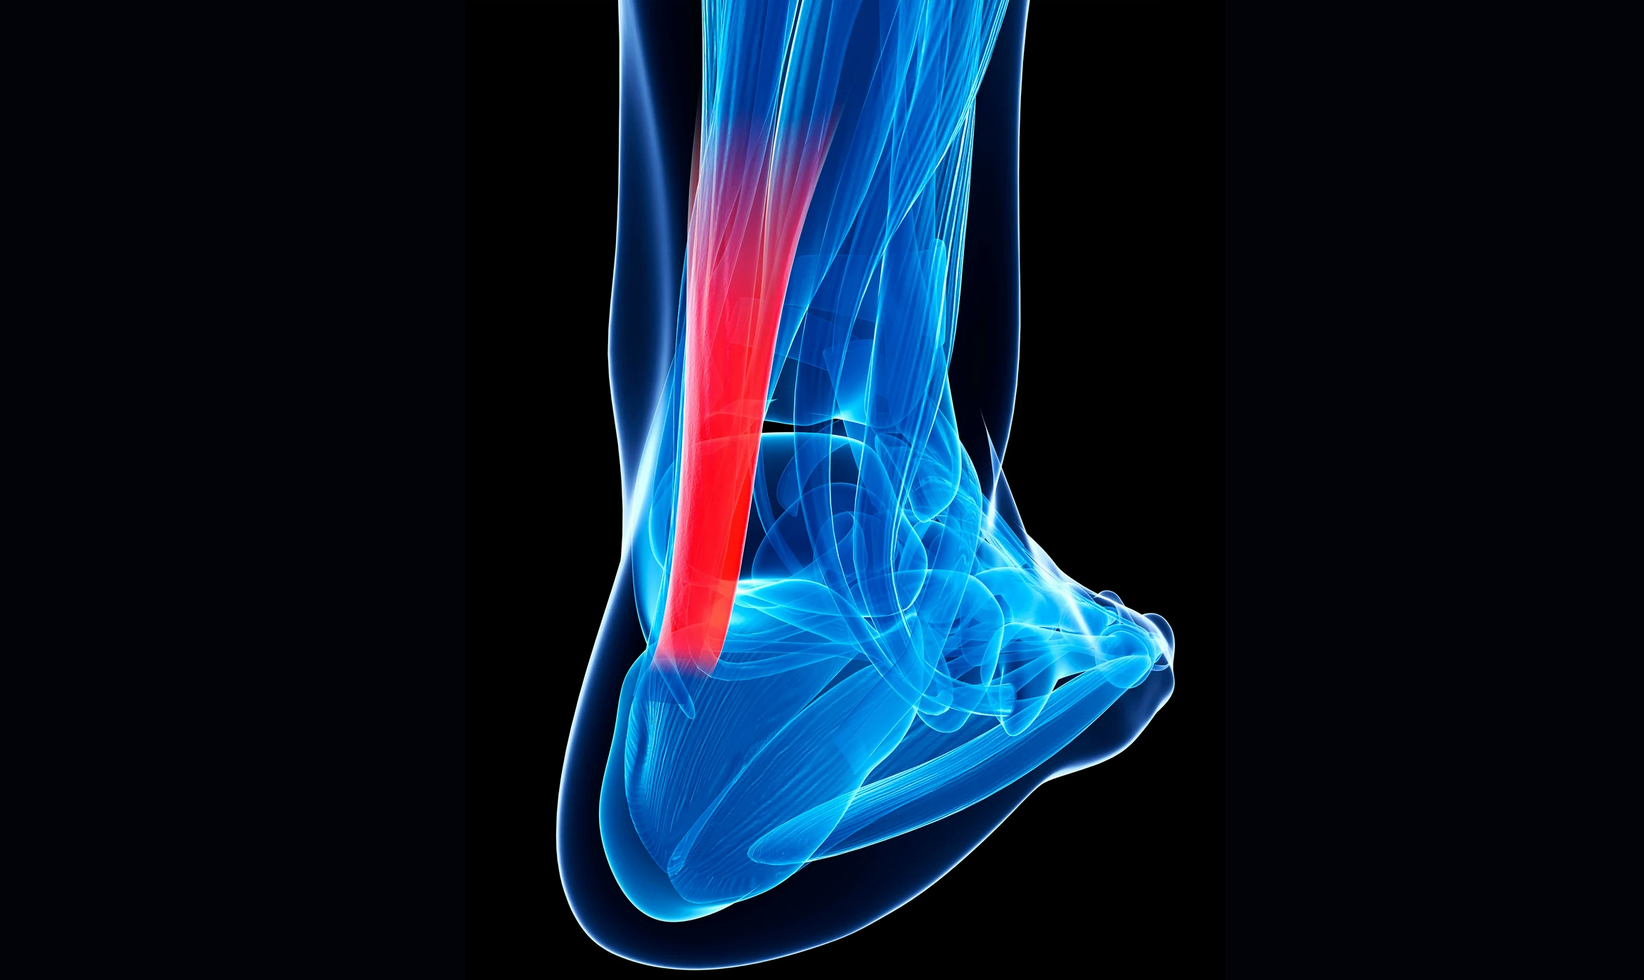

Un esguince de tobillo es una lesión común que sucede cuando los ligamentos que estabilizan las articulaciones del tobillo se estiran más allá de su rango normal o se rompen, generalmente como resultado de una torcedura o un movimiento brusco. Suele producirse al pisar mal, girar el pie de forma repentina o al caer con el pie en mala posición. Los síntomas típicos incluyen dolor, hinchazón, hematoma e inestabilidad. La gravedad del esguince varía según el grado de daño en los ligamentos y el tratamiento puede ir desde reposo y fisioterapia hasta inmovilización temporal, dependiendo del caso.

GRADO DE LESIÓN:

En función de la gravedad de la lesión clasificaremos los esguinces de tobillo en los siguientes grados:

- Grado I (leve): Estiramiento o microdesgarro de las fibras del ligamento sin inestabilidad. Hay dolor leve, inflamación y sensibilidad, pero el paciente puede caminar.

- Grado II (moderado): Desgarro parcial del ligamento. Dolor moderado, hinchazón, hematoma y cierta inestabilidad articular. Dificultad para apoyar el pie.

- Grado III (grave): Rotura completa del ligamento. Dolor intenso, gran inflamación, hematoma e inestabilidad marcada. El paciente no puede apoyar el pie, ni caminar con normalidad.